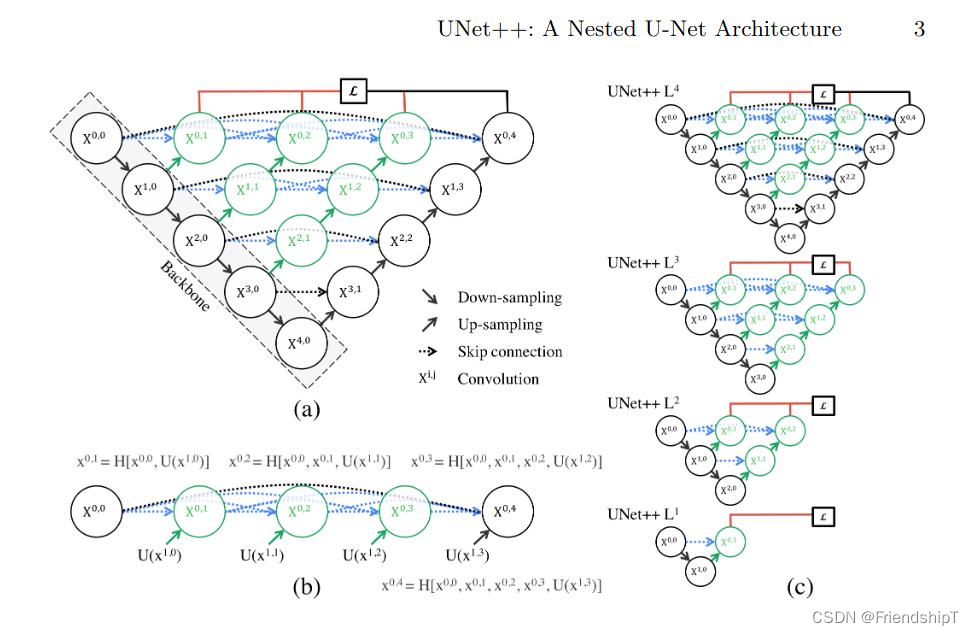

UNet++:一种改进的医学图像分割网络

UNet++是一种基于经典的U-Net网络结构而进一步优化设计的深度学习模型,主要用于医学图像分割和其他高精度像素级分类任务。U-Net因其在保持图像细节的同时有效利用上下文信息的能力而在分割领域广受欢迎,而UNet++则在此基础上提出了更为精细化和深层次的特征融合机制。

UNet++的关键创新点:

密集跳过连接:

- 在UNet中,跳跃连接直接将编码器阶段的低层次特征图与解码器阶段的对应高层次特征图进行拼接或求和操作。

- UNet++引入了更为密集的跳跃连接结构,不仅保留了U-Net的基本跳过连接模式,还增加了多个层级之间的细化连接,使得浅层和深层特征能够更加细致地融合在一起。

嵌套的解码器模块:

- UNet++在解码过程中采用嵌套的方式构建解码器模块,每个解码块内部包含更多的局部跳跃连接,这种设计允许模型更好地捕获不同尺度下的语义信息,并弥合编码器和解码器特征间的语义差距。

特征重采样与融合:

- 在解码阶段,UNet++不是简单地复制编码器的特征图到相应的解码位置,而是采用了逐层渐进式的特征融合策略,这样可以逐步整合不同层次的特征,从而提升分割效果。

结构概览:

- UNet++的整体架构仍然遵循U-Net的编码-解码思路,但其解码器部分包含了更多层次的特征融合模块。

- 每个解码模块都包含一系列卷积层以及与之对应的编码层特征融合单元,这些单元通过卷积运算和跳过连接机制有效地提取和融合多尺度特征。

总结: UNet++通过改进特征提取和融合过程,在保持计算效率的同时提升了分割性能,特别是在处理具有复杂细节和丰富语义信息的图像时表现出色。这一特性使其成为医学图像处理及其他细分领域图像分割任务的重要候选模型之一。